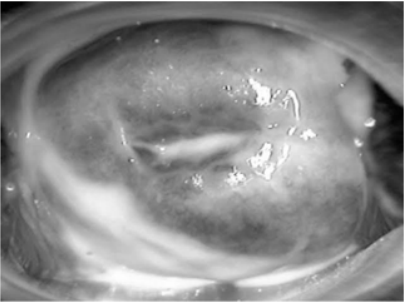

Uma gestante com dezesseis semanas e quatro dias compareceu ao pronto-atendimento com queixa de “corrimento vaginal” há quatro dias. O teste das aminas foi positivo e o exame especular é ilustrado na figura 1. Após a realização de coloração Gram, o resultado pode ser observado na figura 2.

Enunciado 3510882-1

Figura 1

Enunciado 3510882-2